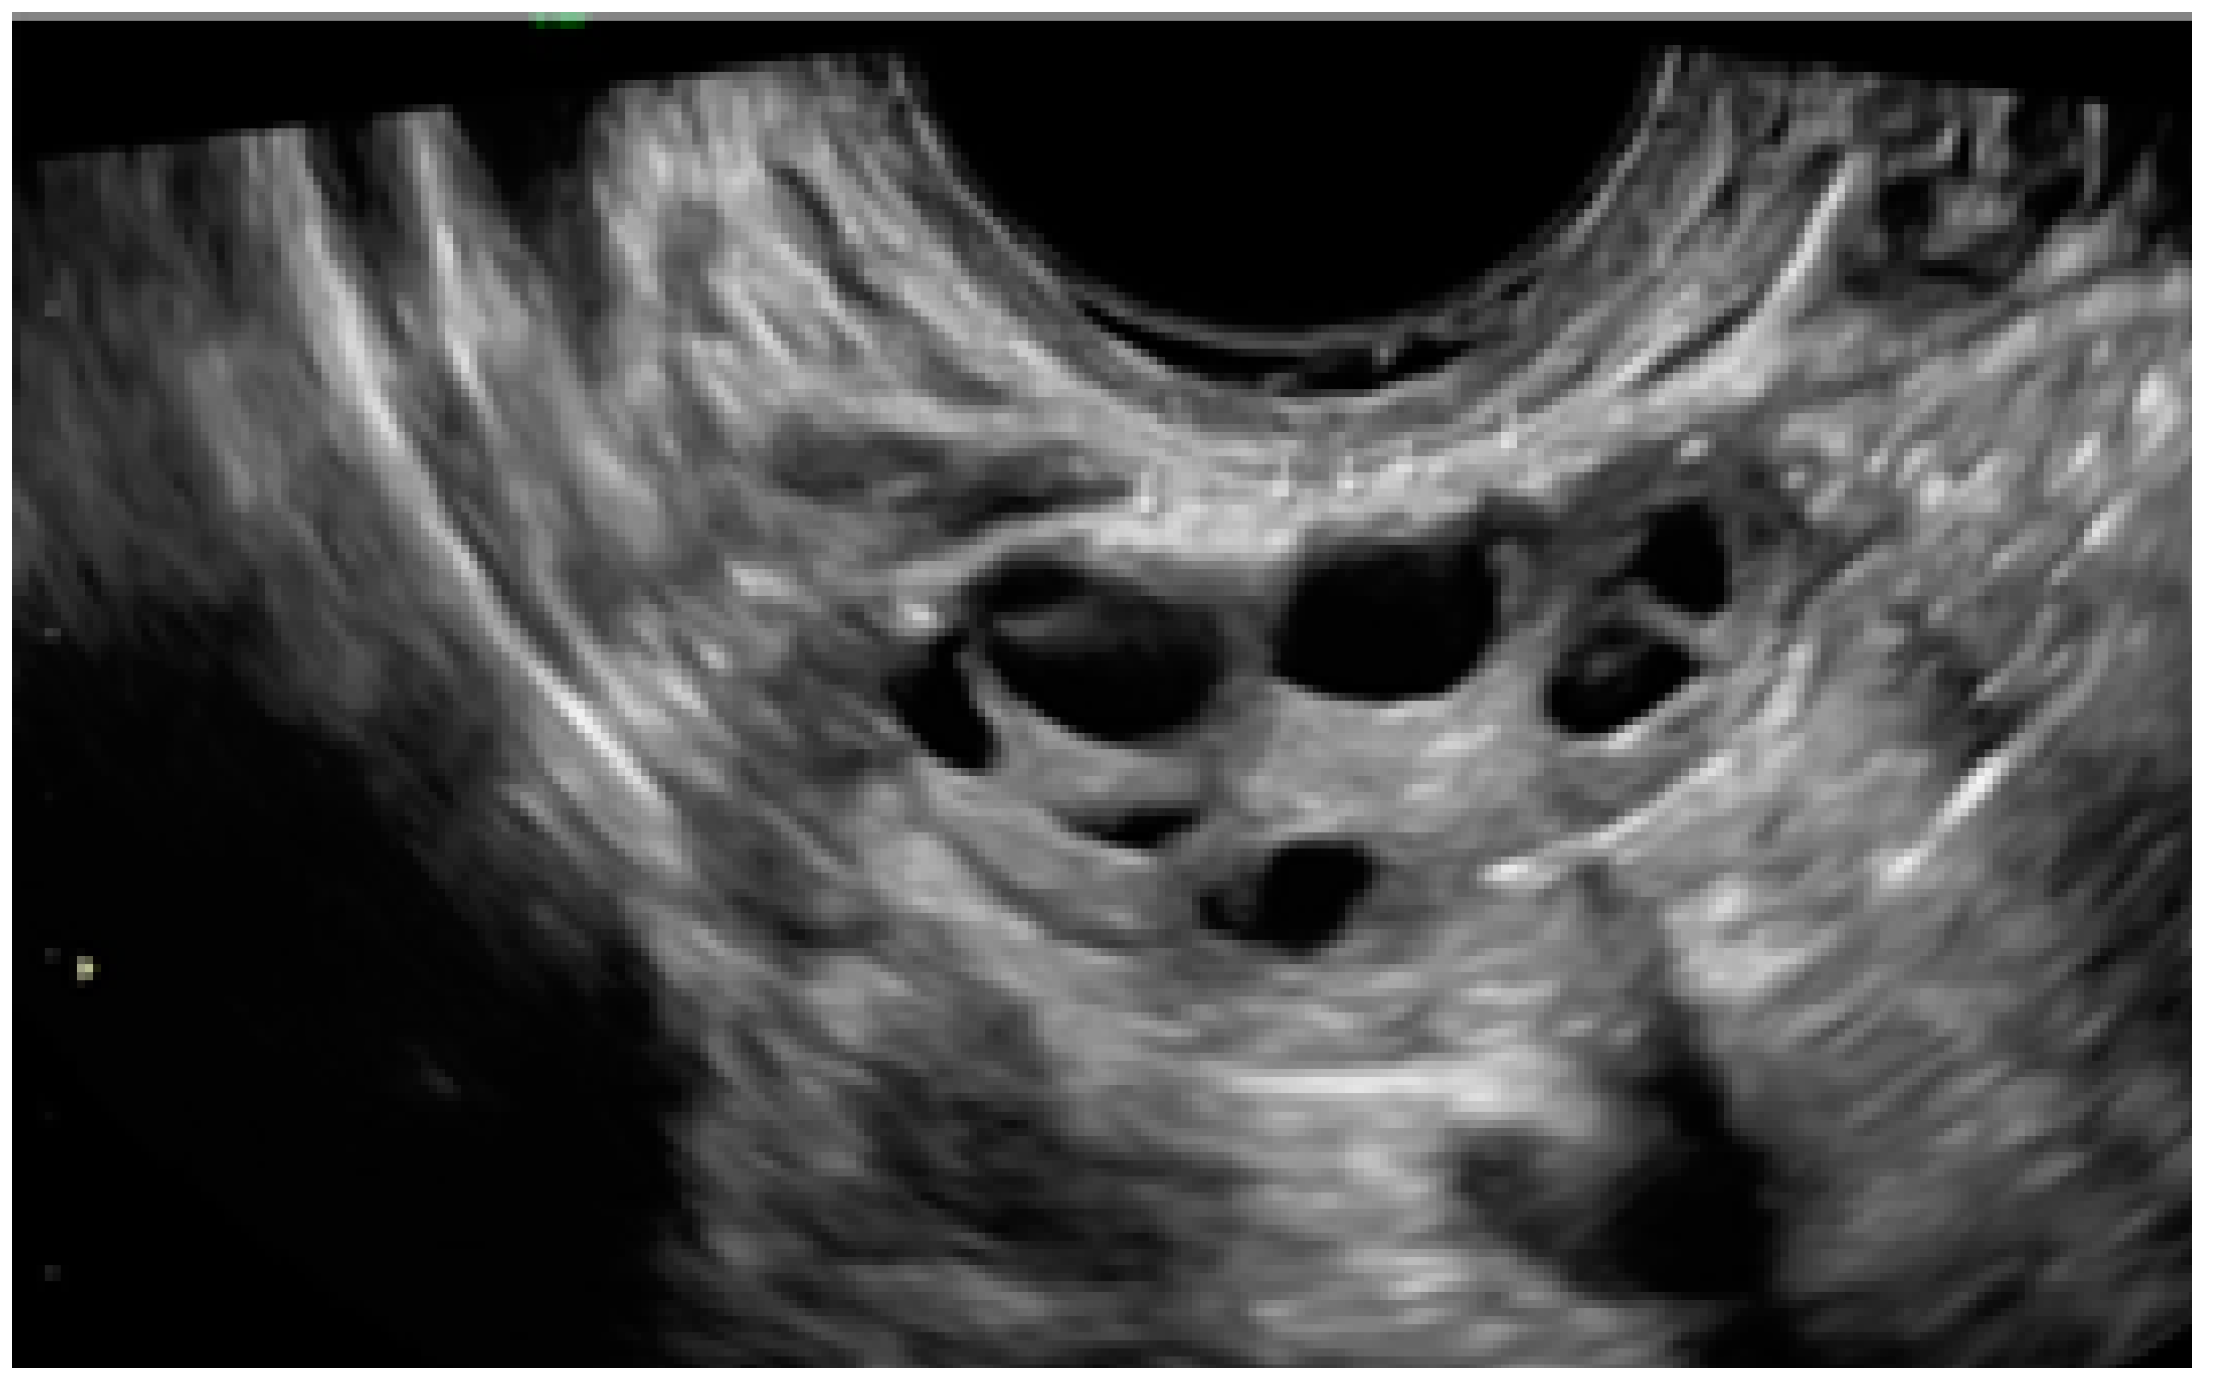

3.3. Cystic Lesions Arranged in a Cluster